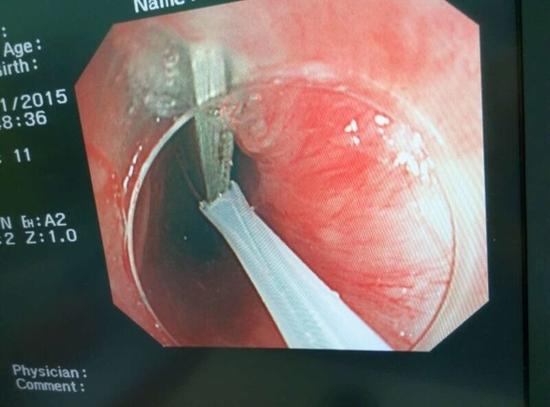

醫(yī)生從華先生胃里取出的鑷子和打火機

手術(shù)中,范醫(yī)生通過胃鏡準確發(fā)現(xiàn)了胃里的鑷子。但讓他驚訝的是,在華先生胃底竟然還躺著三個被腐蝕了的打火機,打火機的金屬部件都已經(jīng)不見了。

隨后,范醫(yī)生先用圈套器套取出了長10厘米的鑷子,再一個一個地取出了打火機。整個取出過程小心謹慎而又一氣呵成,只用了不到10分鐘。